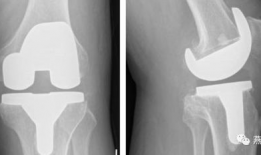

膝关节置换手术视频,从术前准备到术后康复

你有没有想过,当你的膝关节像老化的弹簧一样“嘎吱嘎吱”作响时,会有一种神奇的手术能把它换成一个全新的呢?没错,就是膝关节置换手术...

2025-12-09 37 -